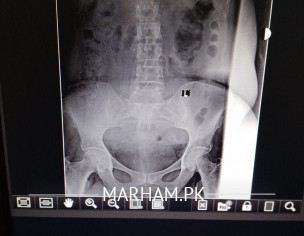

Aoa everyone please guide me about this xray. My mother is having a severe backpain. She did a xray. doctor said xray is normal but there is back patches on both sides and also a big black patch. Please guide me what's that. Thank you

whats wrong with this xray. we have gone through orthopedic surgeon. he didn't tell anything please guide us so we further move